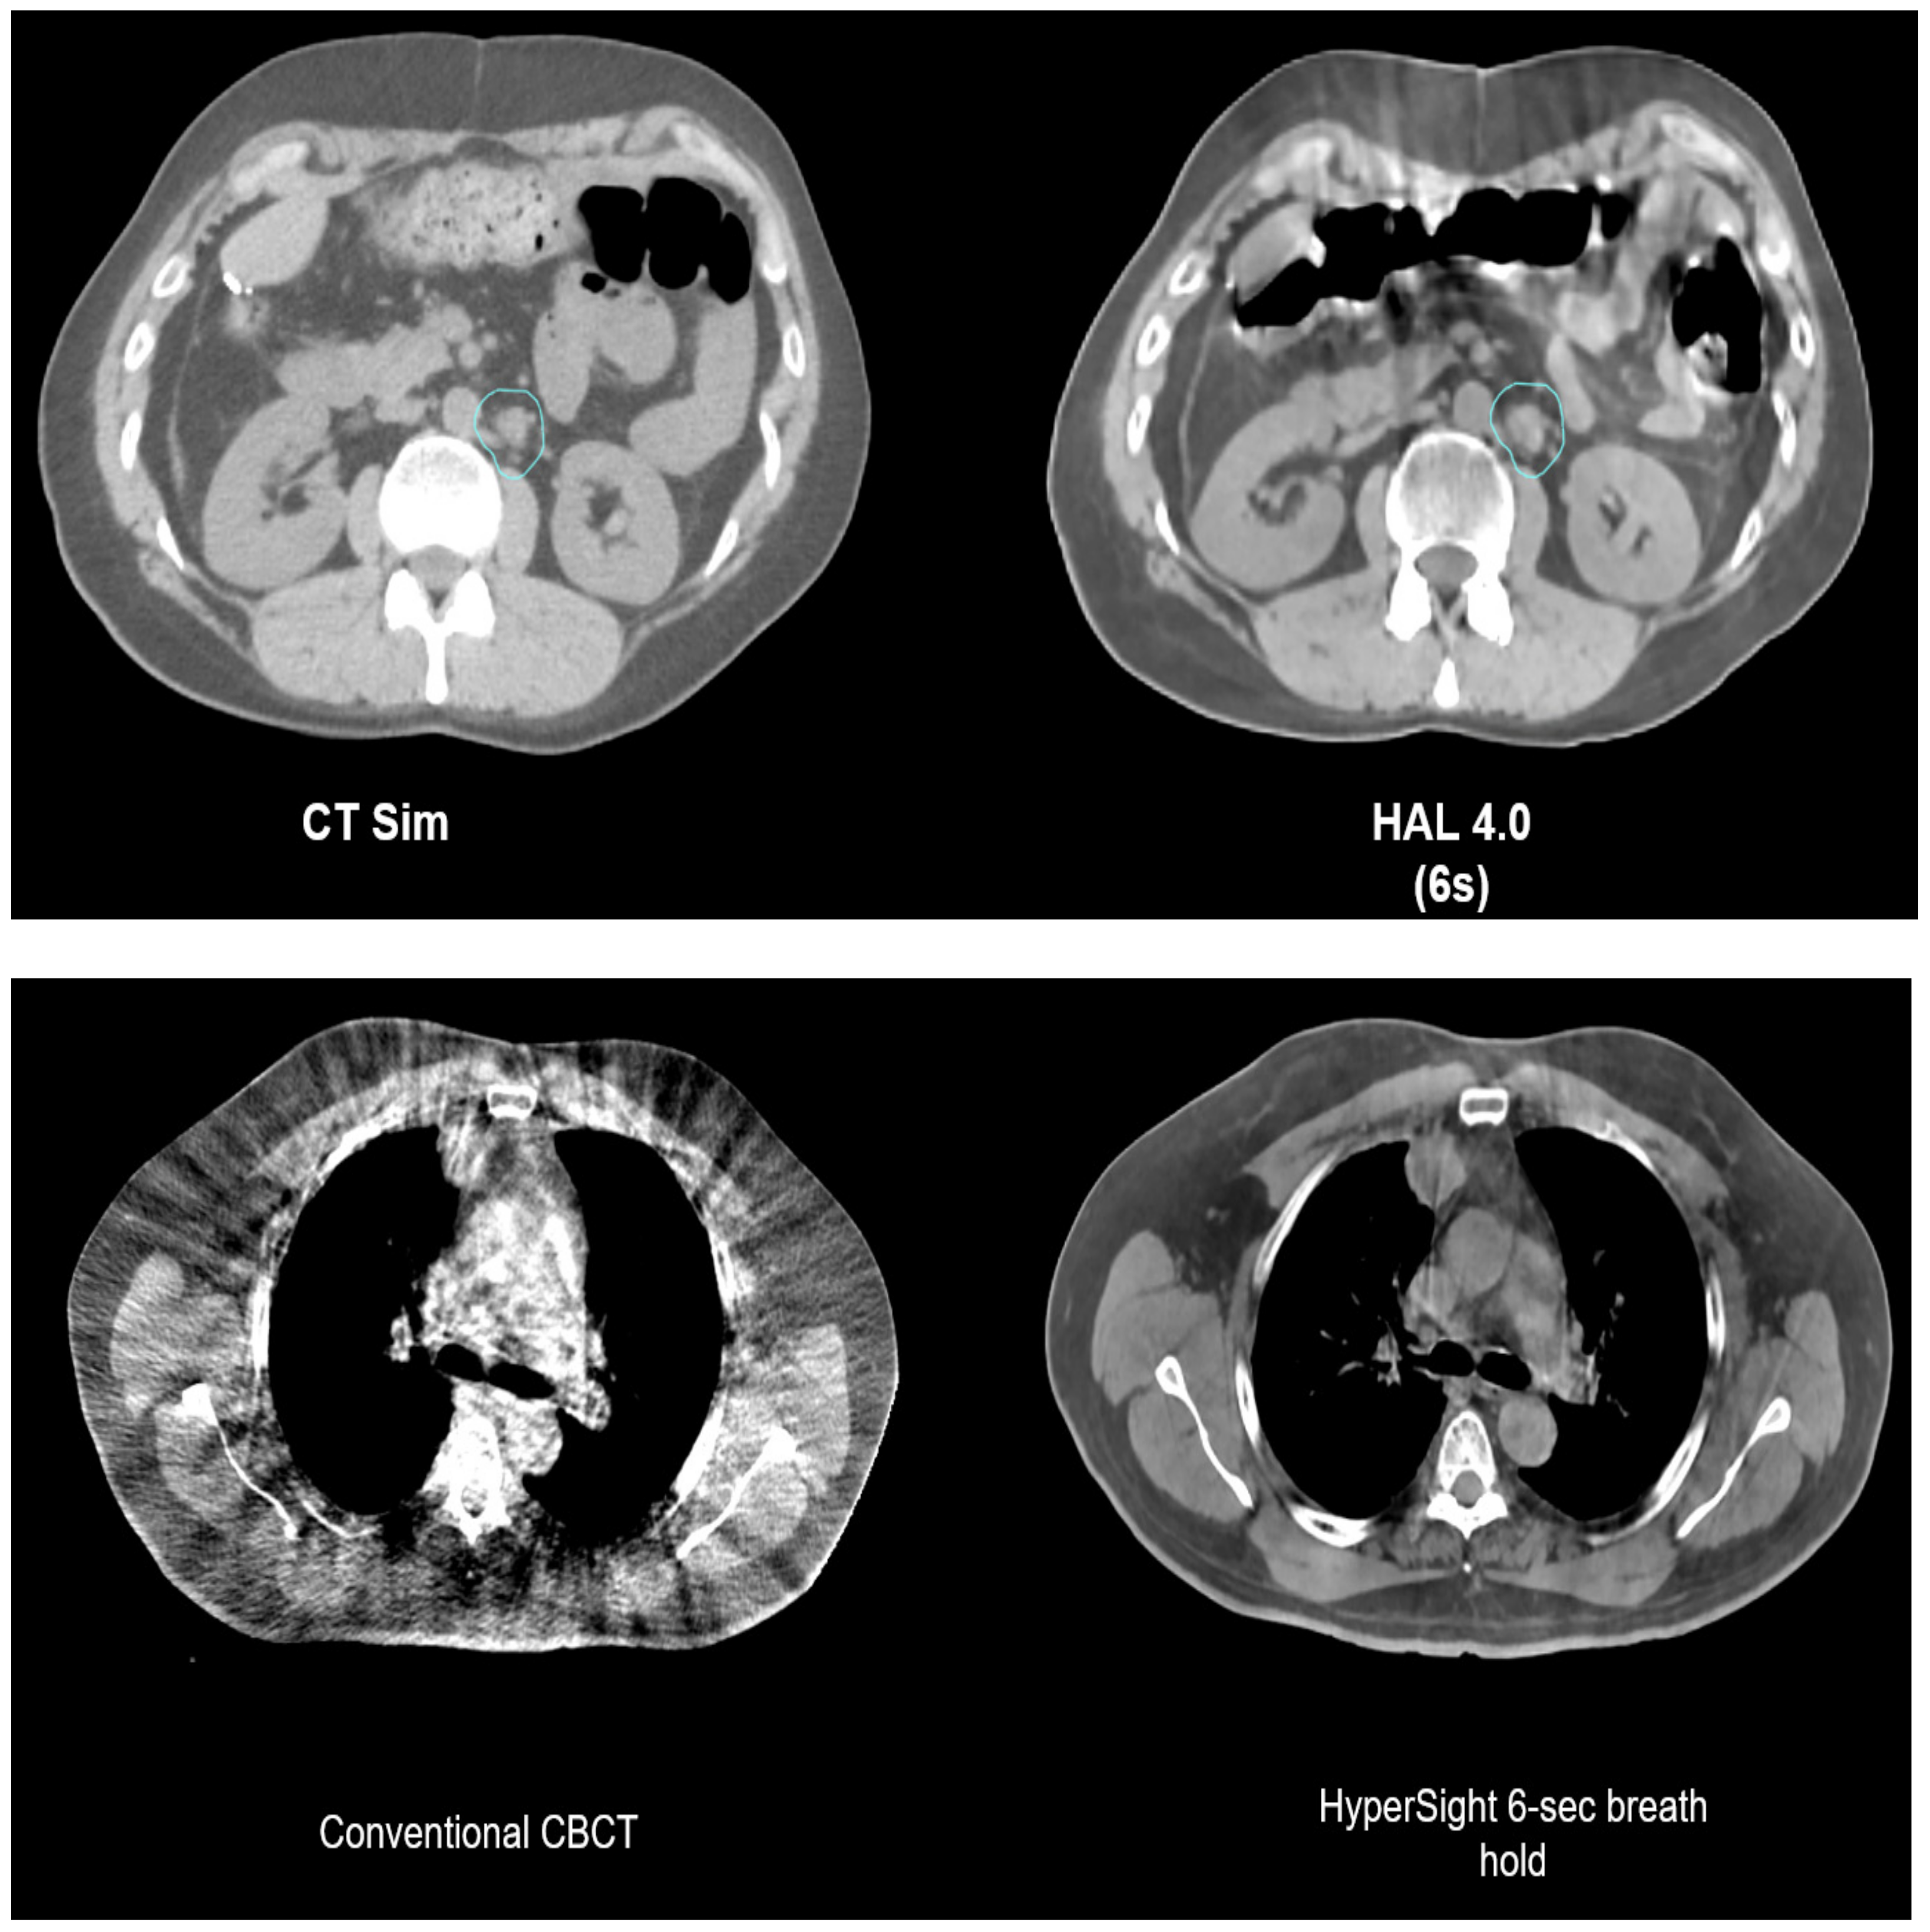

Conventional CBCT, which is used to image patients for CBCT-based ART, has inferior image quality compared to fan-beam CT used for planning, mostly due to higher levels of scatter radiation. To overcome this limitation, the computation of the dose needs to be carried out on a synthetic image generated by applying deformable image registration to align the planned CT with the daily CBCT [33]. The development of iterative CBCT (iCBCT) has enhanced the overall quality of CBCT images, leading to more accurate CBCT-based IGRT. In addition, a forthcoming Ethos 2.0 combined with the new HyperSight CBCT technology (Varian Medical Systems, Palo Alto, CA, USA) anticipated for release in 2024 would possess innovative attributes including a very fast acquisition time down to 6 s, an expanded field of view of up to 70 cm, reduced artifacts, and advanced reconstruction procedures. As shown in the example images in Figure 5, HyperSight provides markedly improved image quality compared with conventional CBCT in terms of higher image contrast, reduced noise, and mitigated artifacts, which may arguably possess image quality almost comparable to the simulation CT. As such, in the new workflow, adaptive planning will be carried out directly on HyperSight CBCTs, bypassing the need for a synthetic CT. The utilization of these novel CBCT images for treatment planning and dose calculation will enable the resolution of some challenges associated with CBCT-based adaptive approaches.

Figure 5.

HyperSight CBCTs. The upper panel compares a simulation CT vs. a HyperSight CBCT (HAL 4.0 with a 6 s acquisition) of the abdomen. HyperSight CBCT shows comparable image contrast as the simulation CT and minimal streaking artifacts from gas pockets and breathing motion. The lower panel compares a conventional CBCT vs. a HyperSight CBCT (breath hold with a 6 s acquisition) of the thorax. The HyperSight CBCT shows much better image contrast and mitigated streaking artifacts and noise. Used with permission from Varian Medical Systems (https://medicalaffairs.varian.com/hypersight, accessed on 31 January 2024).

The primary benefit of CBCT-based ART is its cost-effectiveness, which allows for widespread availability of these systems. Additionally, CBCT-based ART offers shorter treatment sessions compared to MRI or PET. Furthermore, it provides a comparably simpler and more seamless integration with emerging LINAC technologies and X-ray-based AI. The ability to directly plan and calculate dose using the images provided by the new HyperSight CBCT is particularly desirable and potentially eliminates the uncertainty associated with utilizing a synthetic CT. Conversely, CBCT is less effective at differentiating soft tissues that have identical X-ray attenuation coefficients, resulting in reduced contrast in soft-tissue structures. In regions characterized by intricate anatomy or in places where the accurate identification of soft-tissue structures is essential, the poor differentiation of soft tissues in CBCT images may present difficulties. On the other hand, the CBCT-based online ART system Ethos has been found to provide sufficient image contrast and accuracy for conducting effective online ART on abdominal, pelvic, head and neck, and other cancers [34,35,36,37,38]. Furthermore, CBCT lacks the capability to reveal details regarding metabolic activity or functional properties of tissues, as its main purpose is to visualize anatomical structures. Having information regarding metabolic activity could be beneficial for refining treatment plans in specific cancer treatment scenarios, particularly in cases involving ART where real-time adjustments are made depending on changes in tumor features.